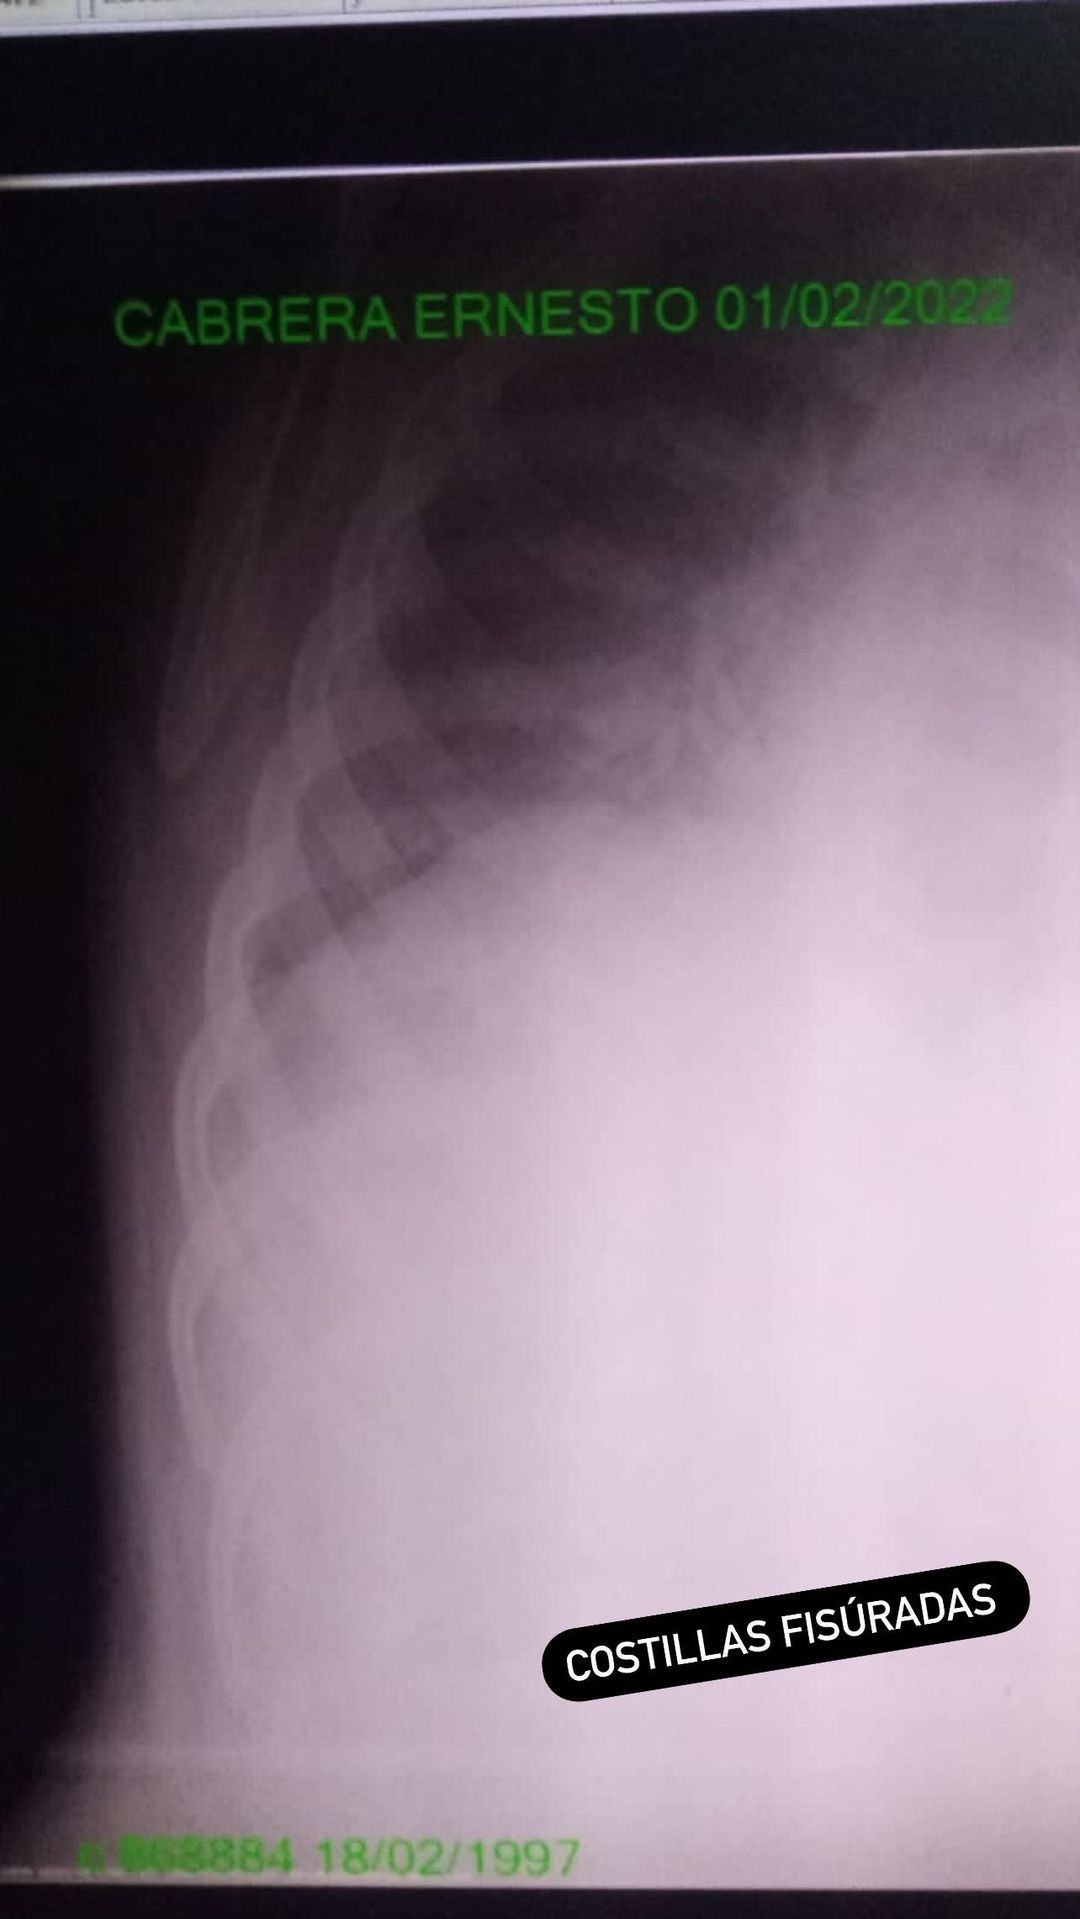

Sobre sus lesiones, Cabrera aseguró que la mayor complicación está en la costilla y que el golpe en la cabeza por ahora no reviste gravedad.